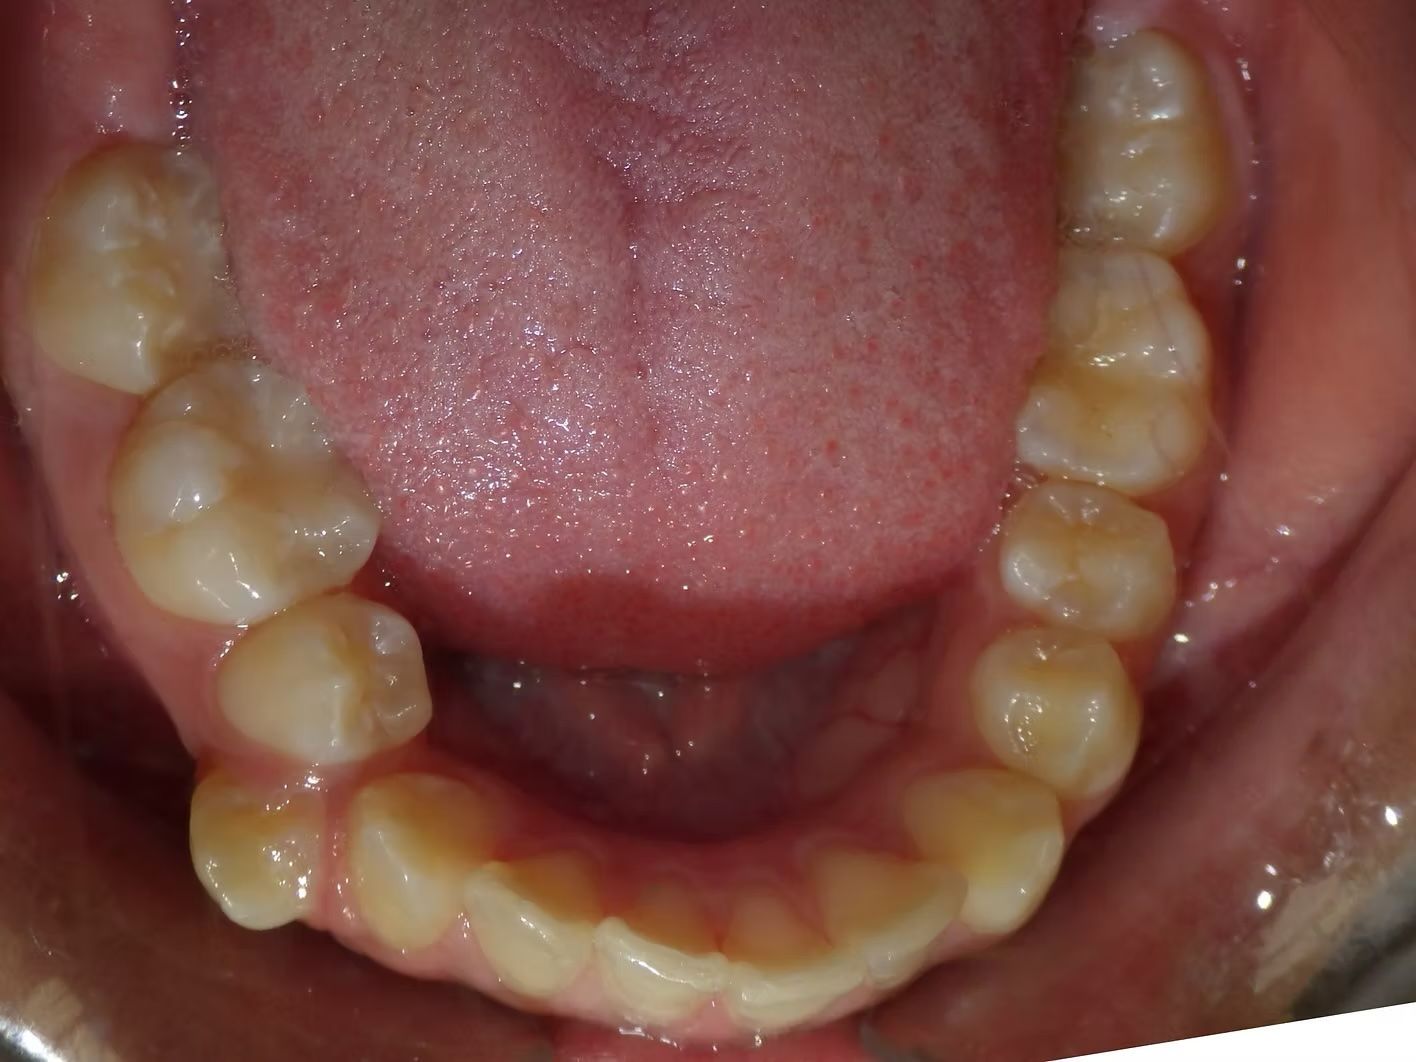

BRIANNA

Brianna's lower left 1st premolar was completely in a brodie bite (outside the normal arch) and her top and bottom teeth were very crowded. Dr. Freedman corrected her bite and crowding without removing any teeth.